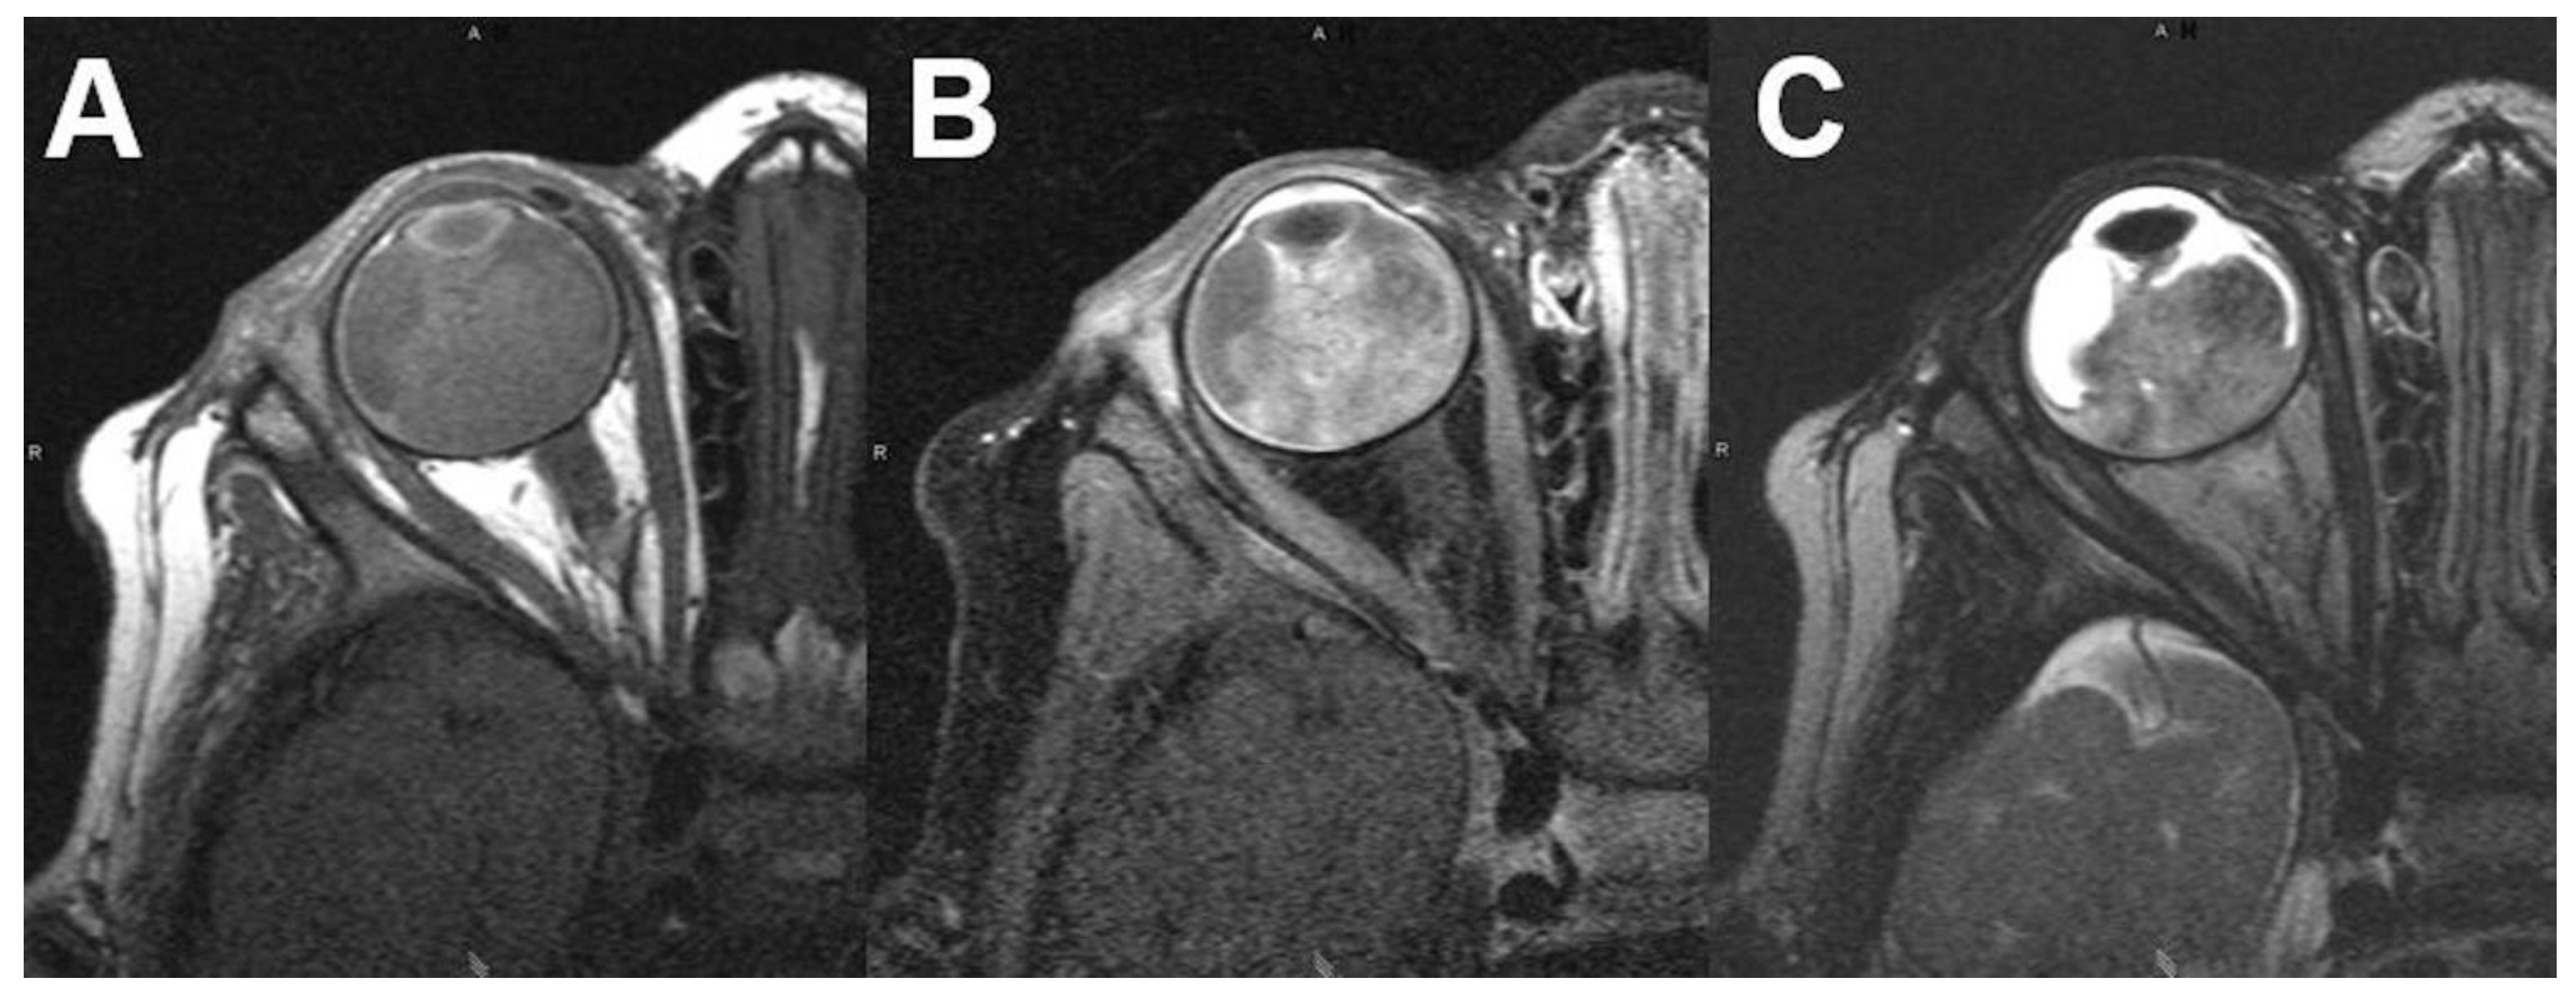

3.1.2. Uveal Melanoma

- Ferreira, T.A.; Jaarsma-Coes, M.G.; Marinkovic, M.; Verbist, B.; Verdijk, R.M.; Jager, M.J.; Luyten, G.P.M.; Beenakker, J.M. MR imaging characteristics of uveal melanoma with histopathological validation. Neuroradiology 2022, 64, 171–184. [Google Scholar] [CrossRef] [PubMed]

- Foti, P.V.; Travali, M.; Farina, R.; Palmucci, S.; Spatola, C.; Raffaele, L.; Salamone, V.; Caltabiano, R.; Broggi, G.; Puzzo, L.; et al. Diagnostic methods and therapeutic options of uveal melanoma with emphasis on MR imaging-Part I: MR imaging with pathologic correlation and technical considerations. Insights Imaging 2021, 12, 66. [Google Scholar] [CrossRef] [PubMed]

- Ferreira, T.A.; Grech Fonk, L.; Jaarsma-Coes, M.G.; van Haren, G.G.R.; Marinkovic, M.; Beenakker, J.M. MRI of Uveal Melanoma. Cancers 2019, 11, 377. [Google Scholar] [CrossRef]